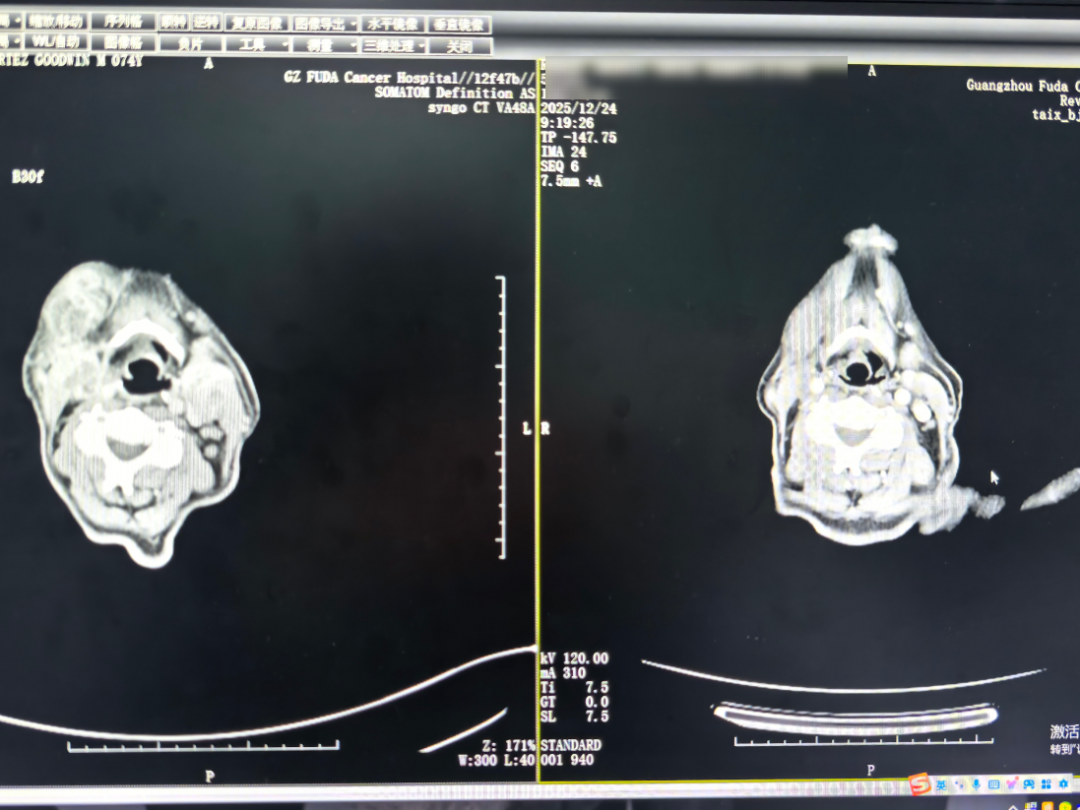

在复大,详细检查显示:肿瘤已侵犯到鼻咽、软腭及右侧肌肉,且伴发出血风险。医疗团队没有采用传统大开刀的方式,而是为他量身制定了一套“组合方案”:通过动脉灌注化疗精准攻击肿瘤,并用介入栓塞术封堵血管、降低出血可能;同时配合静脉滴注PD-1抑制剂,重新激活免疫系统识别和杀伤肿瘤细胞的能力,去对抗癌细胞。

△两个疗程后的CT对比图,口咽肿物、颈部肿块缩小